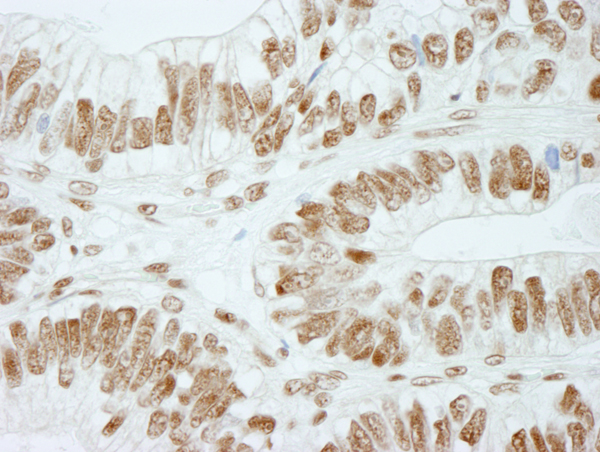

(Detection of human RbBP5 by immunohistochemistry. Sample: FFPE section of human colon adenocarcinoma. Antibody: Affinity purified rabbit anti-RbBP5 (Cat. No. AAA213847) used at a dilution of 1:250. Detection: DAB)